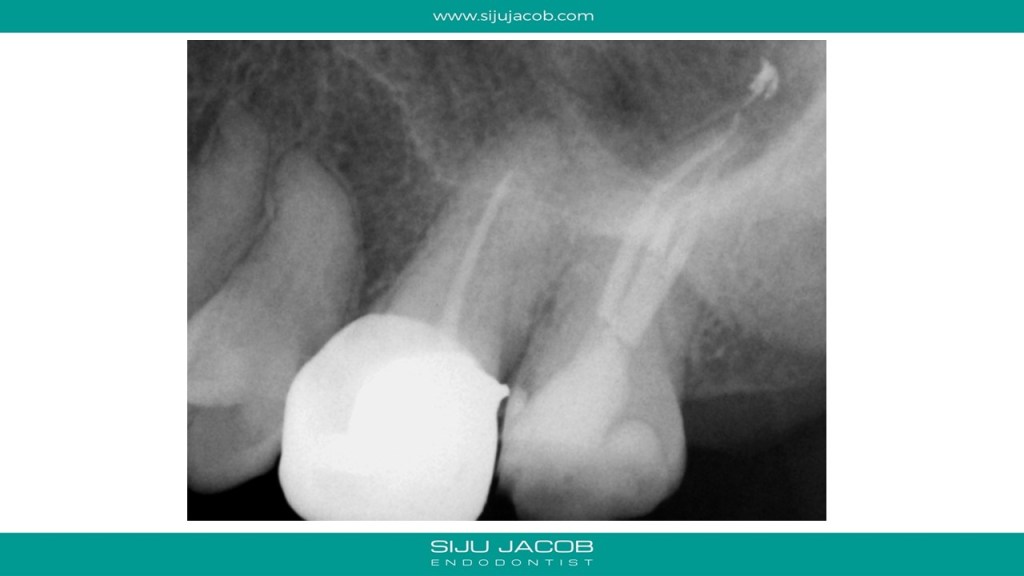

We often see maxillary second molars, which, at first glance seem to have just 2 canals, one Buccal and one palatal. A closer examination of the Buccal canal will often reveal bifurcation into two canals, DB and MB. Here is one such case.